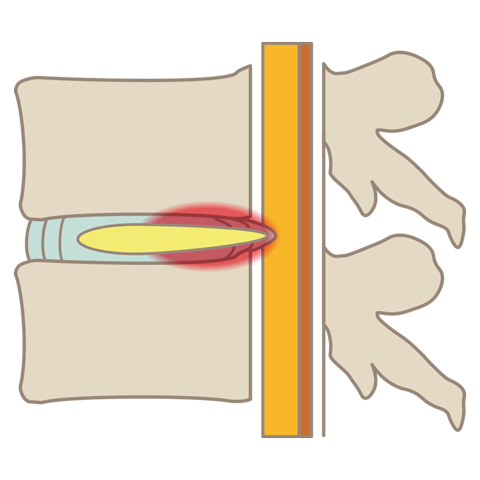

腰椎椎間板ヘルニア

腰椎椎間板ヘルニアとは、背骨の間にある椎間板(ついかんばん)が外に飛び出し、神経を圧迫する疾患です。坐骨神経痛やぎっくり腰などの症状を引き起こします。